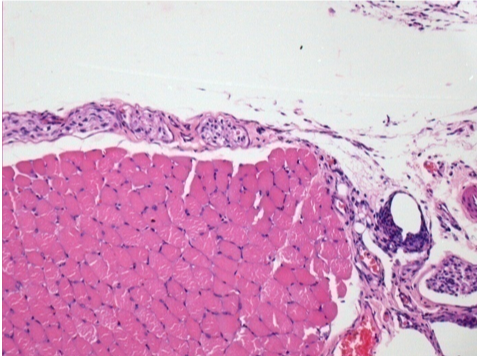

1 mes después de la inyección de Endopeel

1 mes después de la inyección de Endopeel 0,1 ml en el músculo pretibial derecho.

¡Lo que se ve en negro en las imágenes no es una necrosis como podrían imaginar algunos científicos!

De hecho, hay que tener en cuenta 4 conclusiones

- un artefacto de coloración

- una ausencia de necrosis

- una apoptosis

- un proceso biorregenerativo

L : Control-100xD30

R:100xD30

R :400xD30